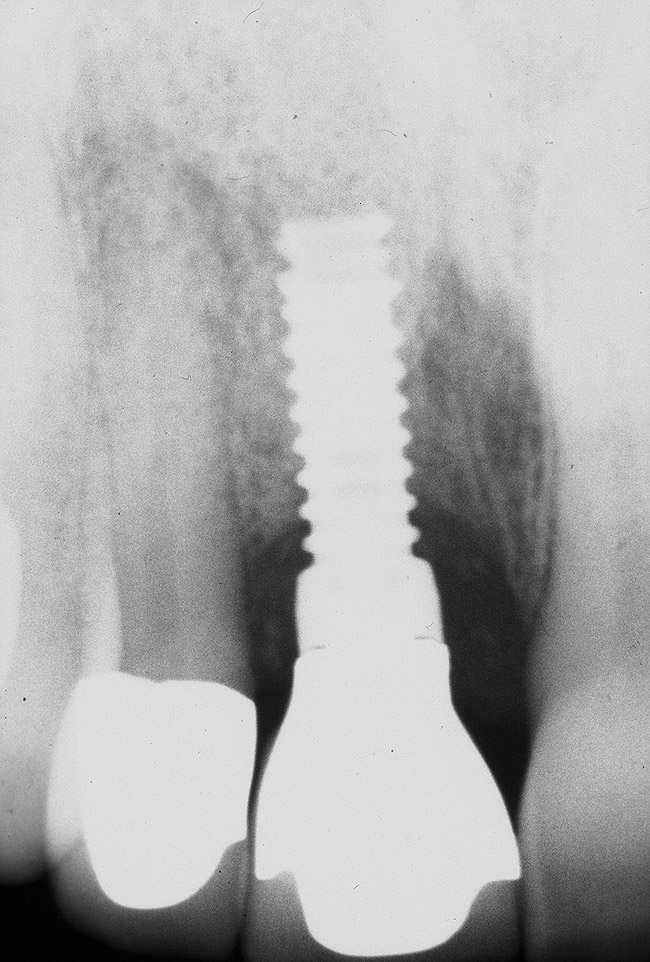

Implant mobility is not a useful diagnostic parameter. If an implant is mobile, it should be considered failed and removed. Conversely, implants may have advanced peri-implantitis with bone loss from 50% to 90% of implant length and still exhibit no mobility when examined clinically (Figure 1).

Figure 1  An implant, 12 mm in length, with advanced peri-implantitis and 10-mm bone loss, exhibiting no mobility.

Figure 1